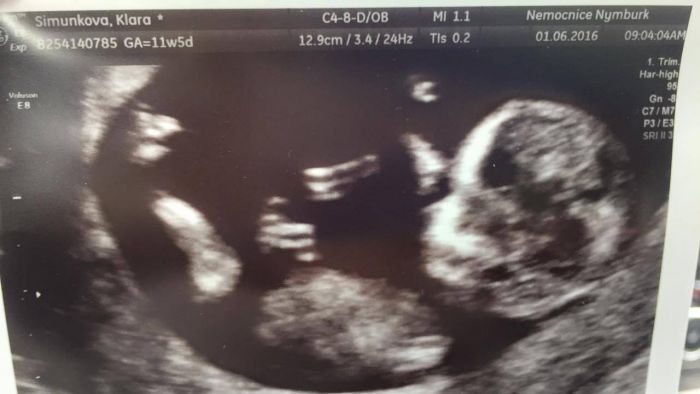

Autor: Klára34 2.6.2016 v 07:27

Ahoj holky...Tak je to za mnou...Termín upraven na 11.12. Dnes Tedy 12+5.Normálně jsem se tam málem rozbrečela...to byla prostě bomba

Klarko, moc krasny fotecky a mozna dalsi holcicka, gratuluju